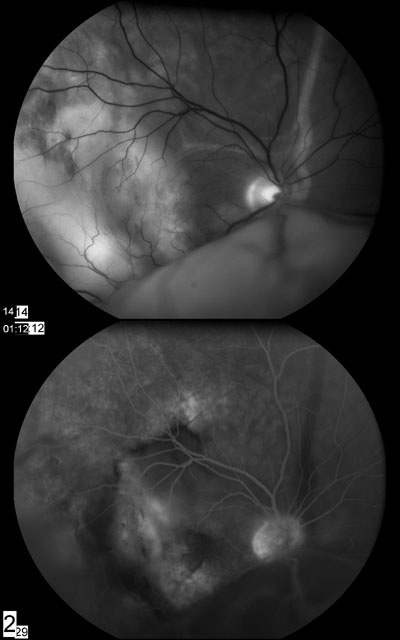

• 眼底检查:右眼出现大疱状、移动的、渗出性、下部视网膜分离,视网膜下无黑色素的脉络膜团块(见图2a及2b)玻璃体清楚。左眼眼底正常(见图1)

图1:左眼眼底正常

图2A:右眼有大面积的渗出性视网膜剥离及颞下区域苍白

图2B:右眼眼底

荧光素血管造影术结果见图3

图3:右眼血管荧光照影图。注意后来被染色的大面积区域实际大于苍白区域本身。